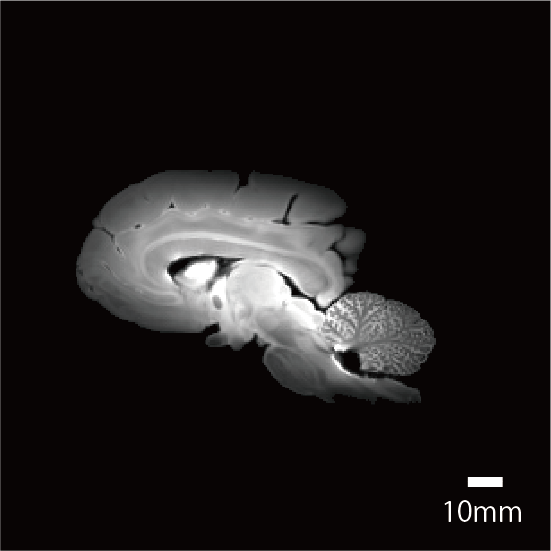

個体・脳標本情報

| 剖検番号 | Pr6082 |

![]() |

|

性別 |

メス | |

死亡時年齢 |

40才前後 | |

| 死亡時体重 | 38000g | |

| 脳重量 | 370g | |

| 脳解剖所見 |

撮像情報

| T2強調画像 | 拡散テンソル画像 | |

| エコー時間 (TE) (秒) | 15 | 28.9 |

| 繰り返し時間 (RT) (秒) | 400 | 300 |

| 励起回数 (NEX) | 2 | 1 |

| 有効視野 (FOV) (mm) | 125, 100, 80 | 125, 100, 80 |

| マトリクスサイズ | 500, 400, 320 | 250, 200, 160 |

| 空間分解能 (µm) | 0.25 | 0.5 |

| b0 | - | 2 |

| 撮像時間 | 7時間 6分 | 77時間 39分 |

脳標本画像

| T2強調画像 |